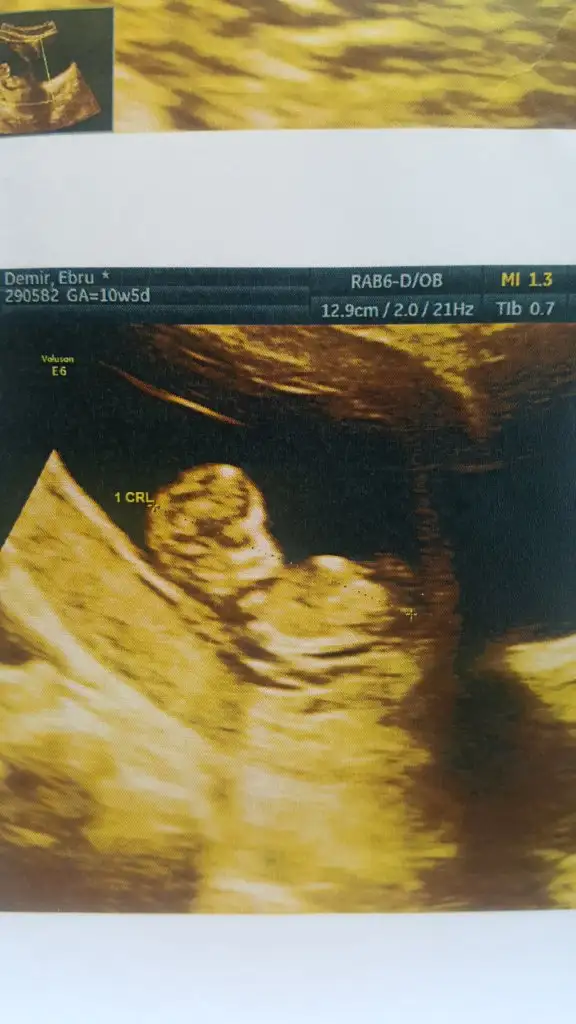

Bebeğimin cinsiyeti

Eklentiler

• 20220913_122703_001.webp

20220913_122703_001.webp

33 KB · Görüntüleme: 72